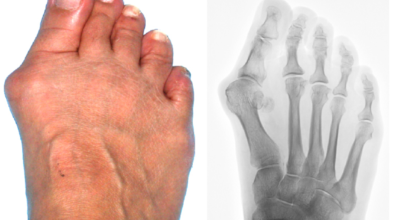

엄지발가락이 두번째 발가락 쪽으로 과도하게 휘고 엄지발가락과 관절을 이루는 중족골은 반대로 안쪽으로 치우치는 변형 되며 발가락이 발등 쪽으로 휘거나 회전(엄지발가락 축을 중점으로 내측으로 회전; 회내)하는 변형을 동반한 삼차원적인 변형을 말합니다.

무지외반증으로 인하여 변형이 심해지면 엄지발가락이 두 번째 발가락과 겹치거나 관절이 탈구되어 전반적으로 디디기 어려운 발이 되기도 합니다. 건강보험심사평가원의 무지외반증 환자 통계를 보면, 세대별로는 40대 이상에서 가장 많으며 성별로는 무지외반증 여성 환자 비율이 남성보다 월등하게 높았다고 합니다.

육안상으로 확연하게 엄지발가락 과 같은 변형 보이며 초기에는 굳은살도 관찰되고 약간의 통증도 있습니다. 엄지발가락 돌출 부위의 통증으로 이 부위가 신발에 자극을 받아 두꺼워지고 염증이 생겨 통증이 발생합니다. 휘어지지 않은 발바닥에 굳은살로 인해 정상 보행이 어렵고 심한 경우 통증으로 인하여 신발 착용은 물론 정상 보행도 어려워집니다. 연속적으로 증상이 악화되면 엄지발가락이 겹쳐지거나 탈구 될 수도 있습니다.

엄지발가락이 옆으로 휘어 관절에 비정상적인 힘이 가해져 퇴행성 관절염이 생길 수 있죠. 그리고 엄지발가락이 지지해야 할 발바닥 압력이 2, 3번째 발가락으로 옮겨지면서 발바닥 쪽에 굳은살이 발생할 수 있고 발가락 뼈 사이의 신경이 붓고 통증이 나타나는 지간신경종이 합병될 수도 있습니다.